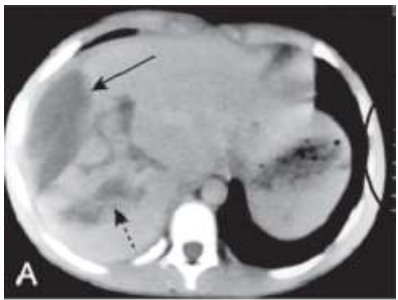

Paciente procura unidade de Urgência com dor em hipocôndrio direito, evolução de 48 hs, após trauma abdominal, acompanhada de náuseas e vômitos e queda do estado geral. Após a abordagem terapêutica foi submetido ao exame de Tomografia do Abdome (imagem abaixo, figura A.), qual o órgão avaliado e o que indicam as setas contínua e descontínua?

FONTE: HERRING, 2019